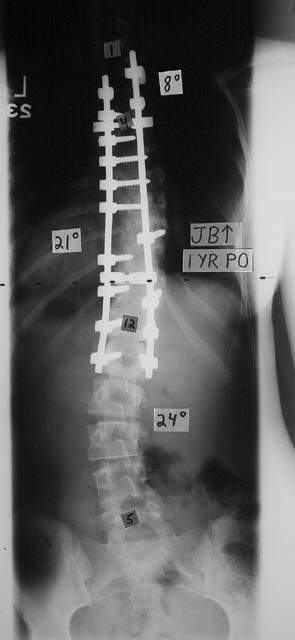

It looked like this:

This x-ray is one year after my surgery. I spent two weeks in the hospital and was released on Thanksgiving Day of November 2000. I escaped with only a handful of numb spots on my right side. Being able to breathe was amazing! One of my lungs, actually, was so used to being squished by my spine that it collapsed in the hospital. Take a bendy straw, bend it tight and try to breathe through it. That’s what it felt like. Doctors couldn’t reinflate my lung, so I travelled by ambulance to a nearby hospital. Soon, I was all right again.